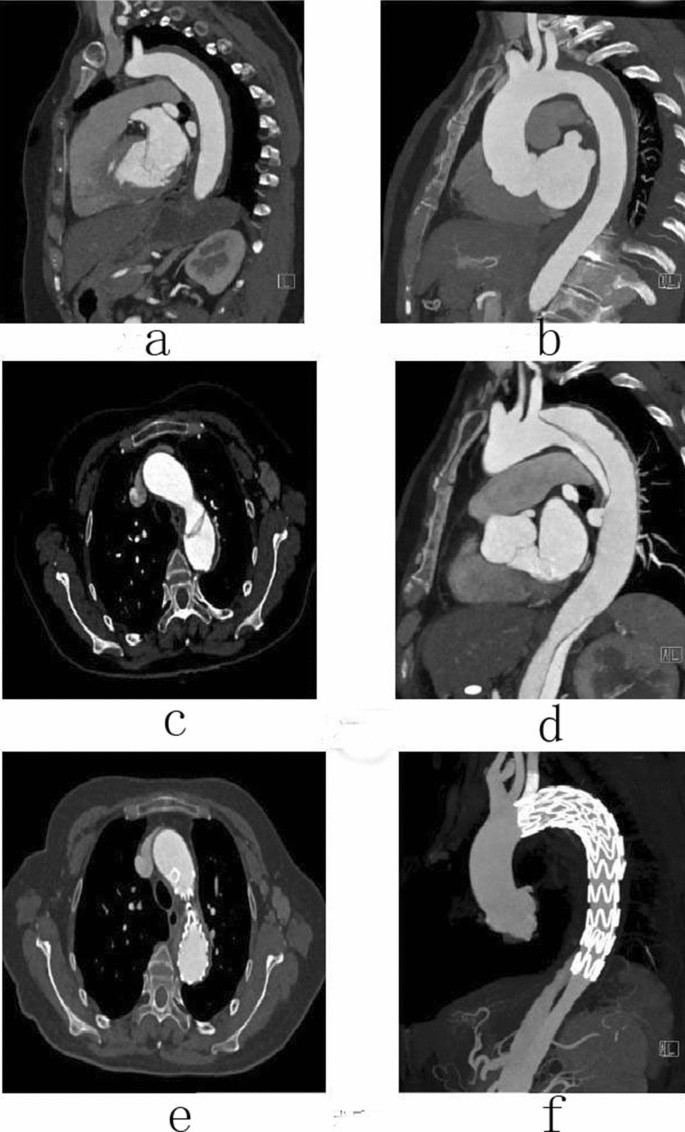

Female, 58 years old, admitted to hospital for “sudden pain in chest for 6 h”, Diagnosis: Stanford type B aortic dissection; Treatment: IMH TEVAR treatment. CTA of the patient in different periods: (a) Admission; (b) 5 days after admission; (c) 16 days after admission; (d) 16 days after admission; (e) 7 days after surgery; (f) 7 days after surgery.